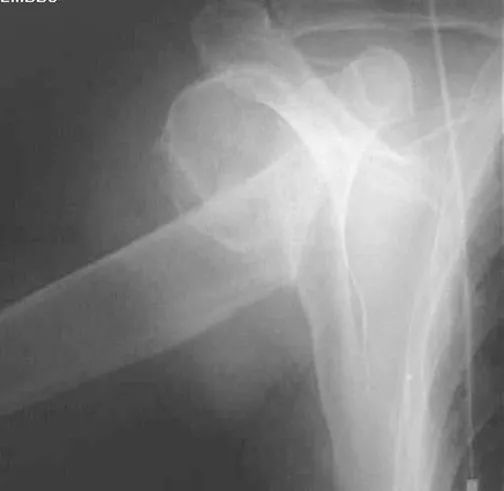

锁骨骨折

常发生在中段。多为横断或斜行骨折,内侧断端受胸锁乳突肌的牵拉常向上后移位,外侧端受上肢的重力作用向内、下移位,形成凸面向上的成角、错位缩短畸形。